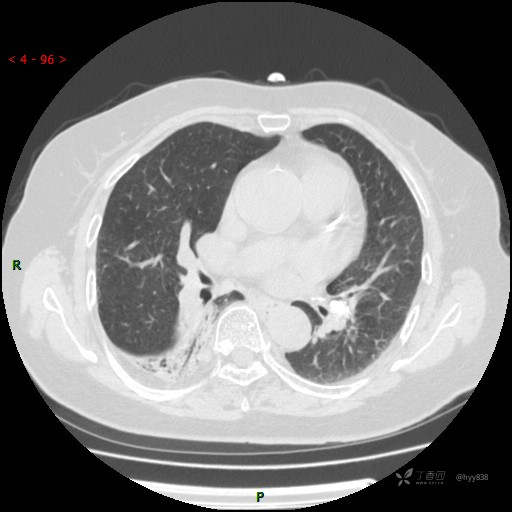

老年女性,肺部病变4年,随诊增大10余天。等你慧眼来诊---结果公布~

主诉:发现肺部病变4年,随诊增大10余天

简要病史:患者4年前因“胸闷、气短”于当地人民医院住院,行胸部CT检查提示右下肺感染性病变可能,进一步行气管镜及抗感染治疗未见明显改变,后未定期复诊。10余天前因“腰痛”再次住院治疗,复查胸部CT提示肺部病变较前明显增大,并伴活动后胸闷、气短,无明显咳嗽、咳痰,无心慌、胸痛,无痰中带血及咯血,无畏寒发热,进一步查全身PET-CT提示肺部慢性感染性病变,但进一步查肺癌标提示CEA明显升高,为求进一步诊治于我院就诊,门诊以“肺部占位性病变”收住入院。 患者自起病来精神、饮食、睡眠尚可,体力下降,体重无明显变化。

辅助检查:CT

临床诊断:可疑肺部占位

胸部CT平扫